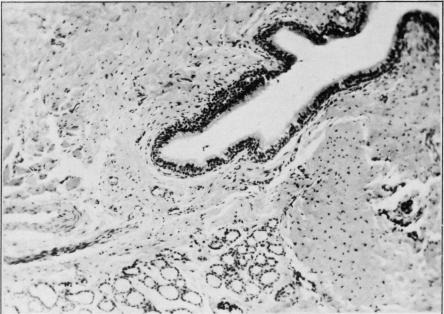

During the 16-year period, July 1, 1959 to June 30, 1975, inclusively, there were only 20 patients with thyroglossal cyst found at the Howard University Hospital (0.03 percent of routine surgicals). There were 12 males and eight females, all of whom were black. Anatomic and histopathologic variations of thyroglossal cysts will be emphasized, and the pitfalls in diagnosis discussed. A brief review of the literature will be presented.

在1959年7月1日至1975年6月30日这16年期间,包括首尾两天,霍华德大学医院仅发现20例甲状舌管囊肿患者(占常规手术患者的0.03%)。患者中有12名男性和8名女性,均为黑人。本文将着重介绍甲状舌管囊肿的解剖学和组织病理学变异,并讨论诊断中的陷阱。还将对相关文献进行简要综述。